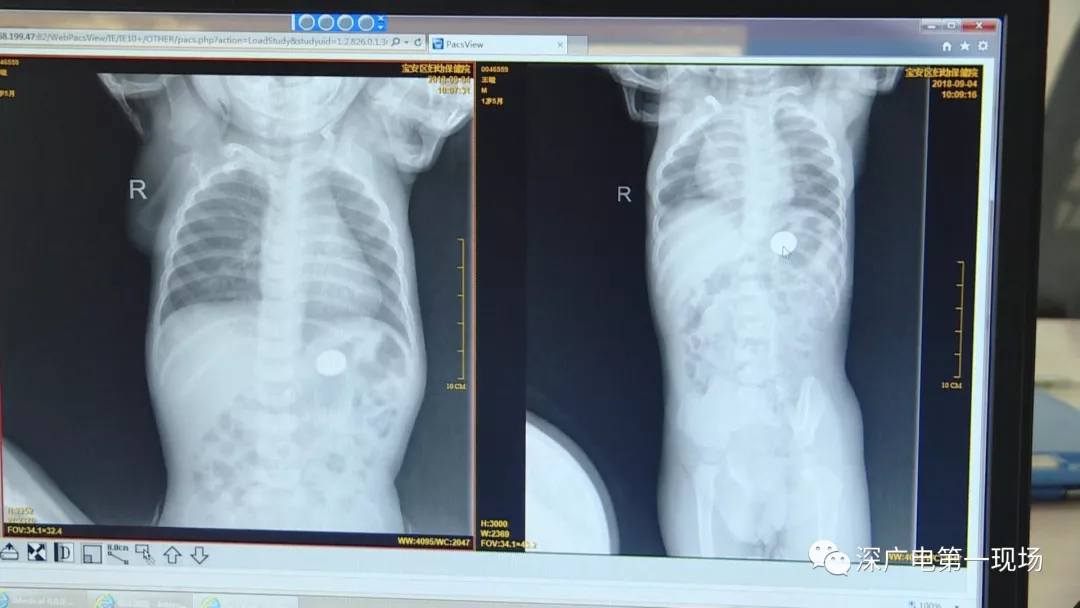

細心的醫(yī)生竟從

孩子的胸片中有了意外發(fā)現(xiàn)

9月4號,一名1歲零5個月的男嬰因在家中摔傷,被父母送到了寶安區(qū)婦幼保健院,醫(yī)生診斷為左側尺橈骨骨折。在進行全麻手術之前,院方例行對嬰兒進行了周身檢查。手術前,兒外科醫(yī)生趙冠聰在查看患者的胸片時,發(fā)現(xiàn)這名嬰兒的胃部有一枚硬幣大小的暗影。

經(jīng)過兩個小時的時間,兒科醫(yī)生郭景濤為患兒取出了藏在胃底的一角錢硬幣。目前,患兒已經(jīng)痊愈出院。